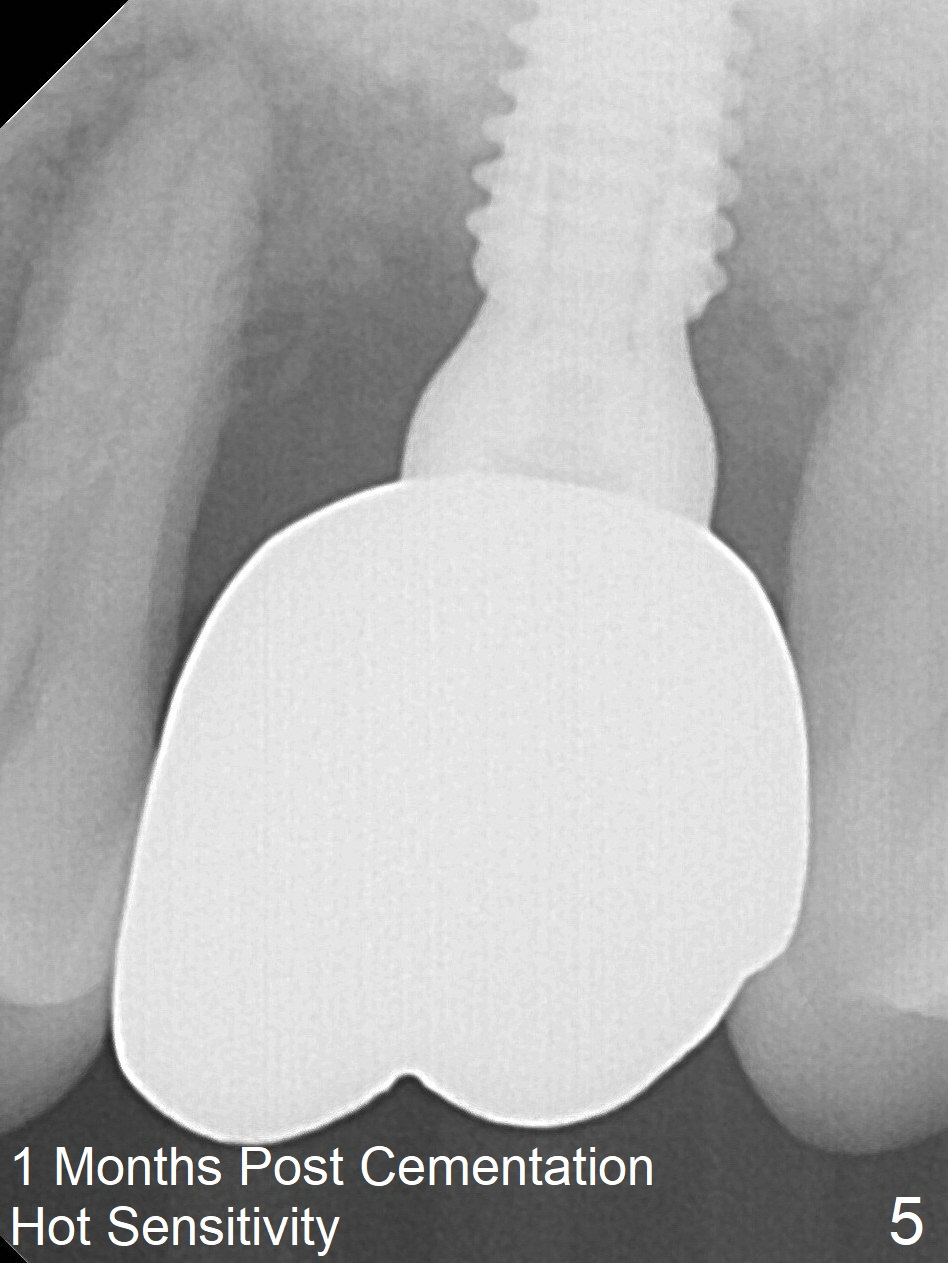

Bone height at #14 two months post exfoliation is ~ 4 mm (Fig.1). Bone expansion is difficult because of dense bone. After drilling, a 4.5 mm tap is inserted with stability (Fig.2). Sinus lift is accomplished with RT3 and autogenous bone prior to placement of a 4.5x8.5 mm implant (Fig.3). Because of flapless surgery and tight and long gingiva, bone graft around the coronal end of the implant is intentionally not placed. A 5.5x5(4) mm abutment is immediately placed for an immediate provisional. (Fig.4). Take PA and impression when the patient returns. The provisional dislodges 3.5 months postop (Fig.4); impression is taken. The patient reports hot sensitivity and pain after meal at the implant site (Fig.5). After removal of the implant crown/abutment, she feels better. If not, it seems necessary to extract the tooth #13 for a 13 mm long implant with a mill abutment (Fig.6).